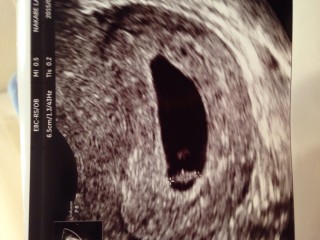

前回初診の際は5w1dだったので胎嚢だけ確認できていましたが、今回7w2dで赤ちゃんの姿と心拍確認できました!! 初めて姿形を見て感動しちゃいました。 先生は見慣れてるから心拍確認できてるね~。って言ってたけど、私は全然わからなかったです(笑) 右のリングが卵黄嚢、左が胎児。 まだどちらが頭とかお尻とかわからないそうです!